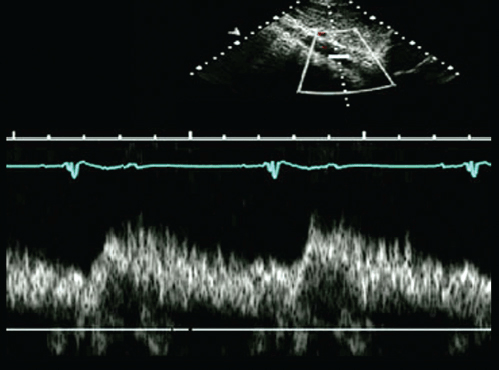

This pulse wave doppler finding was obtained in the descending aorta. What does it represent?

Aortic Coarctation